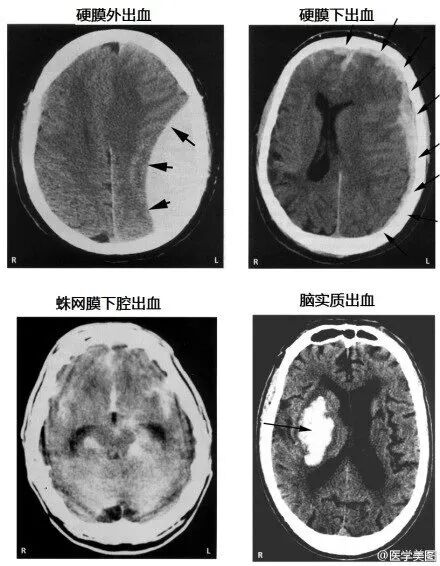

13.各种颅内出血

15.几种类型脑出血的CT表现